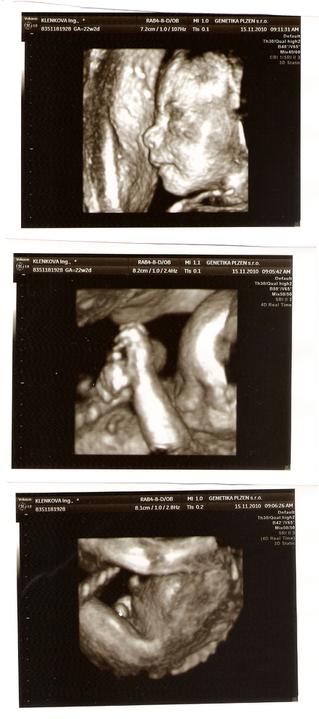

Mimísek o sobě konečně dává pořádně vědět. I tatínka už kopnul do ruky a do ucha:o).